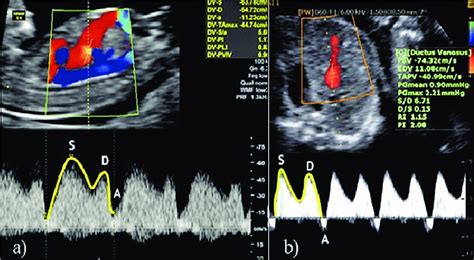

Grupul caz a inclus nou-născuții care au fost născuți la apariția fluxului absent/inversat în diastolă în arterele ombilicale (AO), iar grupul de control a inclus sugarii născuți la apariția undei A inversate/absente în ductus venosus (DV). Nou-născuții au fost urmăriți până la externarea din spital pentru monitorizarea apariției complicațiilor precoce.

Criteriile de includere pentru RCIU cu debut precoce au fost: greutatea fetală estimată (GFE) < percentila a 3-a; vârsta gestațională mai mică de 32 de săptămâni la momentul diagnosticului; și evaluarea Doppler anormală a arterelor ombilicale (AO), arterei cerebrale medii (ACM) sau ductus venosus (DV). Toți sugarii incluși au fost născuți pe baza parametrilor Doppler.

Datele au fost extrase din fișele medicale electronice ale pacienților. Diagnosticul a fost stabilit, iar toate ecografiile în timpul sarcinii și studiile Doppler au fost efectuate de un medic specialist în medicina materno-fetală. Vârsta gestațională a fost stabilită prin ecografie de trimestru I. Greutățile fetale estimate și percentilele au fost calculate utilizând formula Hadlock. Măsurătorile Doppler au fost obținute din arterele ombilicale (AO) și ductus venosus (DV) în conformitate cu standardele uniforme.

În mod tipic, Doppler-ul arterei ombilicale nu este inclus în protocoalele de management pentru RCIU cu debut precoce, până la 30-32 de săptămâni de gestație. În schimb, clinicianul se bazează pe alți indicatori ai sănătății fetale, cum ar fi traseul frecvenței cardiace fetale (FCF), profilul biofizic și velocimetria Doppler a ductus venosus.

În contrast, indicele de pulsatilitate al ductus venosus și variația pe termen scurt a frecvenței cardiace fetale sunt cunoscuți ca predictori importanți ai momentului optim al nașterii înainte de 32 de săptămâni de gestație și corelează cu rezultatul fetal la naștere în anumite studii.